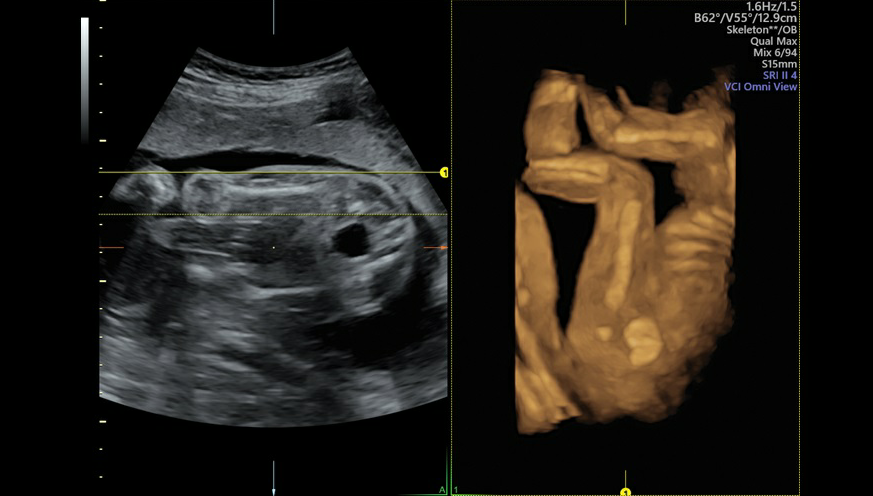

GE VOLUSON E8是目前世界上先进的彩色超声设备,被誉为“神奇彩超”,是筛查胎儿畸形的尖端设备。它提供了包括腹部、血管、小器官、产科、妇科、泌尿科、新生儿和儿科等多领域的多方面的应用。能够显示未出生的宝宝的实时动态活动图像,或者其它人体内脏器官的实时活动图像。通过四维彩超,孕妈妈躺在床上,就可以通过对面的显示屏直接和宝宝见面,还可以看到宫内胎儿,如打哈欠、伸懒腰、吮手指等等奇妙的动作。

Voluson E8的3D/4D容积超声技术已经得到了世界范围的广泛认可,Voluson E8除了保持Voluson产品在3D/4D的成像技术优势以外,在2D图像质量,彩色灵敏度方面有很大提高外,在核心技术如探头、波束形成器、成像模式、人机工程方面,均有了革命性的提高。该系统满足了临床超声医学专家在图像质量、人机工程、工作流程、腔内探头等几个方面提出的期待和希望。

在妇产超声行业,3D/4D技术已经得到了成熟的应用。Voluson E8作为该领域*专业的档的超声诊断仪,拥有多项独有的和的技术,除了继续保持其在妇产超声领域的旗舰产品的地位以外,在腹部领域,同样具有优异的图像质量。

Voluson产品由具有60年医用超声、20年容积超声的Kretz工厂研制。该工厂在医用超声研制尤其是容积超声的研制上,一直来都引领着这个行业的发展和进步,并保持了的标准。包括Voluson 730系列,世界上台便携式容积超声诊断仪Voluson i ,和目前医用超声行业端的产品Voluson E8,离线的3D/4D数据分析系统4D View和针对产前诊断的妇产超声数据库管理系统ViewPoint为妇产超声行业提供了完整的产品和技术解决方案。